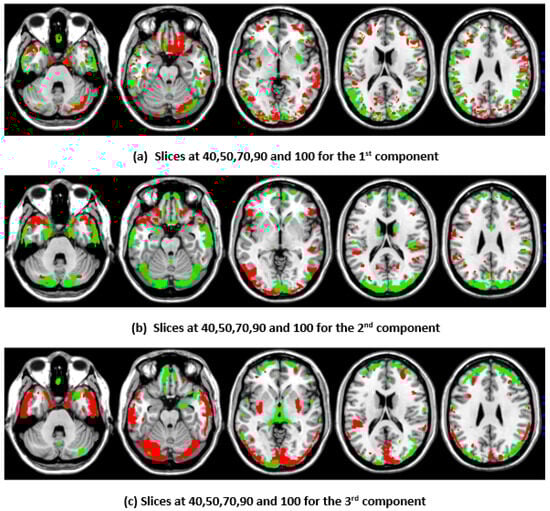

3.4. Top Brain Regions Contributing to CCA and DCCAE Components

To illustrate the brain regions, the top PCs of the first three significantly correlated GM and FA components were plotted for both the CCA results and the DCCAE results. To plot the brain regions, the CCA/DCCAE components were traced back to PCA components using the weight matrix of CCA/DCCAE, and the top PCA components were then mapped to the brain regions.

Figure 1 and Figure 2 depict GM and FA regions for CCA, respectively, while Figure 3 and Figure 4 portray GM and FA regions for DCCAE, respectively, with green indicating positively correlated GM and FA regions and red indicating negatively correlated regions. The GM regions identified via the first component of CCA with their respective volume in cubic centimeters (cc) include the middle temporal gyrus (12.1 cc), pre-central gyrus (14.5 cc), middle frontal gyrus (14.6 cc), superior frontal gyrus (2.0 cc), and sub-gyral regions (12.7 cc). The second component highlights the cuneus (27.3 cc), middle occipital gyrus (10.6 cc), superior frontal gyrus (6.3 cc), lingual gyrus (13.4 cc), and superior temporal gyrus (8.4 cc). The third component encompasses the superior frontal gyrus (27.2 cc), middle frontal gyrus (12.6), cuneus (23.6), superior temporal gyrus (10.8), middle occipitalgyrus (16.0 cc), and thalamus (17.4 cc). Similarly, the first component of DCCAE reveals Cuneus (15.4 cc), middle temporal gyrus (22.1 cc), precentral gyrus (15.6 cc), middle frontal gyrus (20.1 cc), superior temporal gyrus (6.8 cc), inferior parietal lobule (17.3 cc), and superior frontal gyrus (29.2 cc). The second component identifies cuneus (19.6 cc), middle occipital gyrus (11.1 cc), superior frontal gyrus (30.4 cc), middle frontal gyrus (20.1 cc), sub-gyral (9.1 cc), postcentral gyrus (9.5 cc), precuneus (6.0 cc), and middle temporal gyrus (10.3 cc). The third component includes the middle temporal gyrus (23.7 cc), precentral gyrus (11.0 cc), cuneus (29.0 cc), lingual gyrus (6.3 cc), middle occipital gyrus (14.3 cc), inferior frontal gyrus (2.3 cc), postcentral gyrus (10.8 cc), and inferior parietal lobule (6.8 cc).

When examining the direct similarity between components of CCA and DCCAE, we found that most of the CCA components (for both GM and FA) have high and significant correlations (shown in Table 3 and Table 4) with some of the DCCAE components. For example, CCA GM component first is significantly and negatively correlated to DCCAE GM components first and second, and it is positively correlated to DCCAE GM component third. Similar results were observed for FA components; CCA FA component first was linked to DCCAE FA components first and second negatively and component third positively. The negative correlation observed in Table 3 and Table 4 does not indicate a fundamental contradiction in the relationship between GM and FA features. Instead, it suggests that, for the same brain region, CCA encodes a change in one direction (an increase or a decrease), while DCCAE encodes it in the opposite direction. However, the underlying GM-FA association remains consistent across both models. This difference in sign can be further illustrated in Figure 1 and Figure 3, where the first components from CCA and DCCAE show similar spatial patterns, particularly in the posterior occipital region, but the color representation differs, indicating an increase in one model and a decrease in the other.

We also examined the contributing brain regions of components that shared the same brain regions. The top PCs of the CCA and DCCAE components highlighted common regions for GM and FA. The first CCA component correlates with the first, second, and third DCCAE components. The brain regions of the first CCA components include the middle temporal gyrus, precentral gyrus, middle frontal gyrus, superior temporal gyrus, and sub-gyral while DCCAE’s first component identified the middle temporal gyrus, middle frontal gyrus, and sub-gyrus, DCCAE’s second component identified middle temporal gyrus, and middle frontal gyrus, and DCCAE’s third component identified the superior temporal gyrus and precentral gyrus. Similarly, common FA regions were also observed for CCA FA components and DCCAE FA components. The brain regions of the first CCA components include the corticospinal tract, anterior thalamic radiation, and the forceps minor, and DCCAE’s first, second, and third components identified brain regions pointed out by the first component of CCA.

Figure 3. First, second, and third components of GM identified through DCCAE.